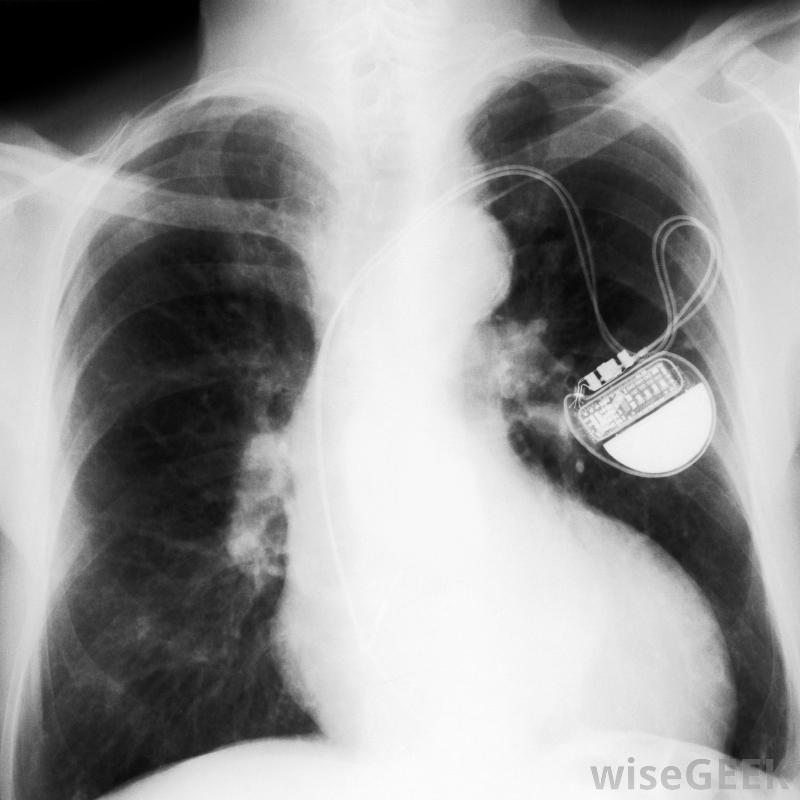

一些心律失常的人需要起搏器的帮助。避免起搏器问题的一种方法是遵循医生。这可能包括电话随访,在这个过程中,电话和一个特殊的装置被用来捕捉起搏器的数据并通过电话线传输。定期去看医生也有助于发现起搏器或其电池的问题。电话随访通常每一两个月进行一次,但是你至少可以每年去看医生。然而,具体的维护计划可能因患者而异。

起搏器可以永久性地监测心脏和心律在心房和心室许多人认为接触微波炉等家用电器会导致起搏器出现问题。实际上,微波炉、电视、电脑和普通电话不太可能干扰起搏器。然而,为了避免起搏器出现问题,你最好不要把手机放在衬衫的胸袋里,因为这可能会损害起搏器的正常功能。但是,一般来说,让起搏器与起搏器保持至少6英寸(约15厘米)的距离有助于防止问题的发生你的起搏器也可能受到强磁场的影响。例如,与产生强磁场的电弧焊设备和医疗机械保持一定距离,可以避免起搏器出现问题。一些工业电机也可能干扰起搏器的正常工作,您最好也避免它们核磁共振扫描也可能损害一个人的起搏器的正常功能。因此,一些人可能宁愿避免核磁共振成像。然而,在某些情况下,磁共振成像可能是诊断和治疗医疗条件的一个重要部分。为了避免磁共振成像引起的起搏器问题,您的医生可能会采取特殊措施来保护您并尽可能限制扫描。此外,您的医生可能会帮助您确定是否为了测试的好处而考虑进行核磁共振检查的风险